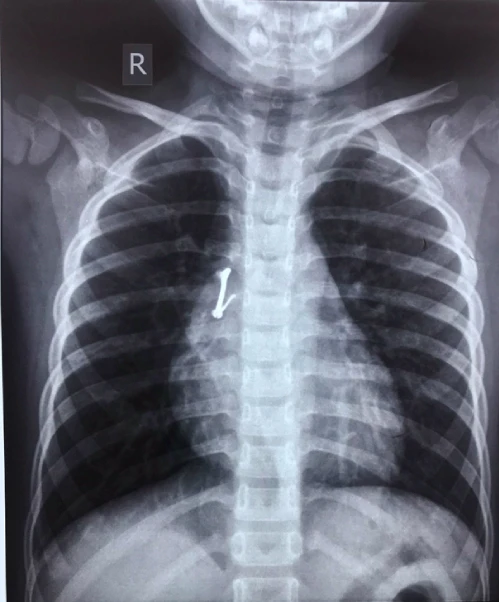

Tuy nhiên, khi chụp X-quang ngực, các bác sĩ mới phát hiện bé có một dị vật ở phế quản của phổi bên phải. Ban đầu, ekip điều trị đã chỉ định nội soi phế quản gắp dị vật cho bé nhưng bất thành do dị vật nhỏ, cứng đã mắc kẹt, dính chặt vào mô của đường thở, nếu cố gắng lấy ra có thể gây vỡ mạch máu, tràn khí, nguy đến tính mạng.

Vị trí chiếc móc khóa trong phổi bé trai. Ảnh: BVCC